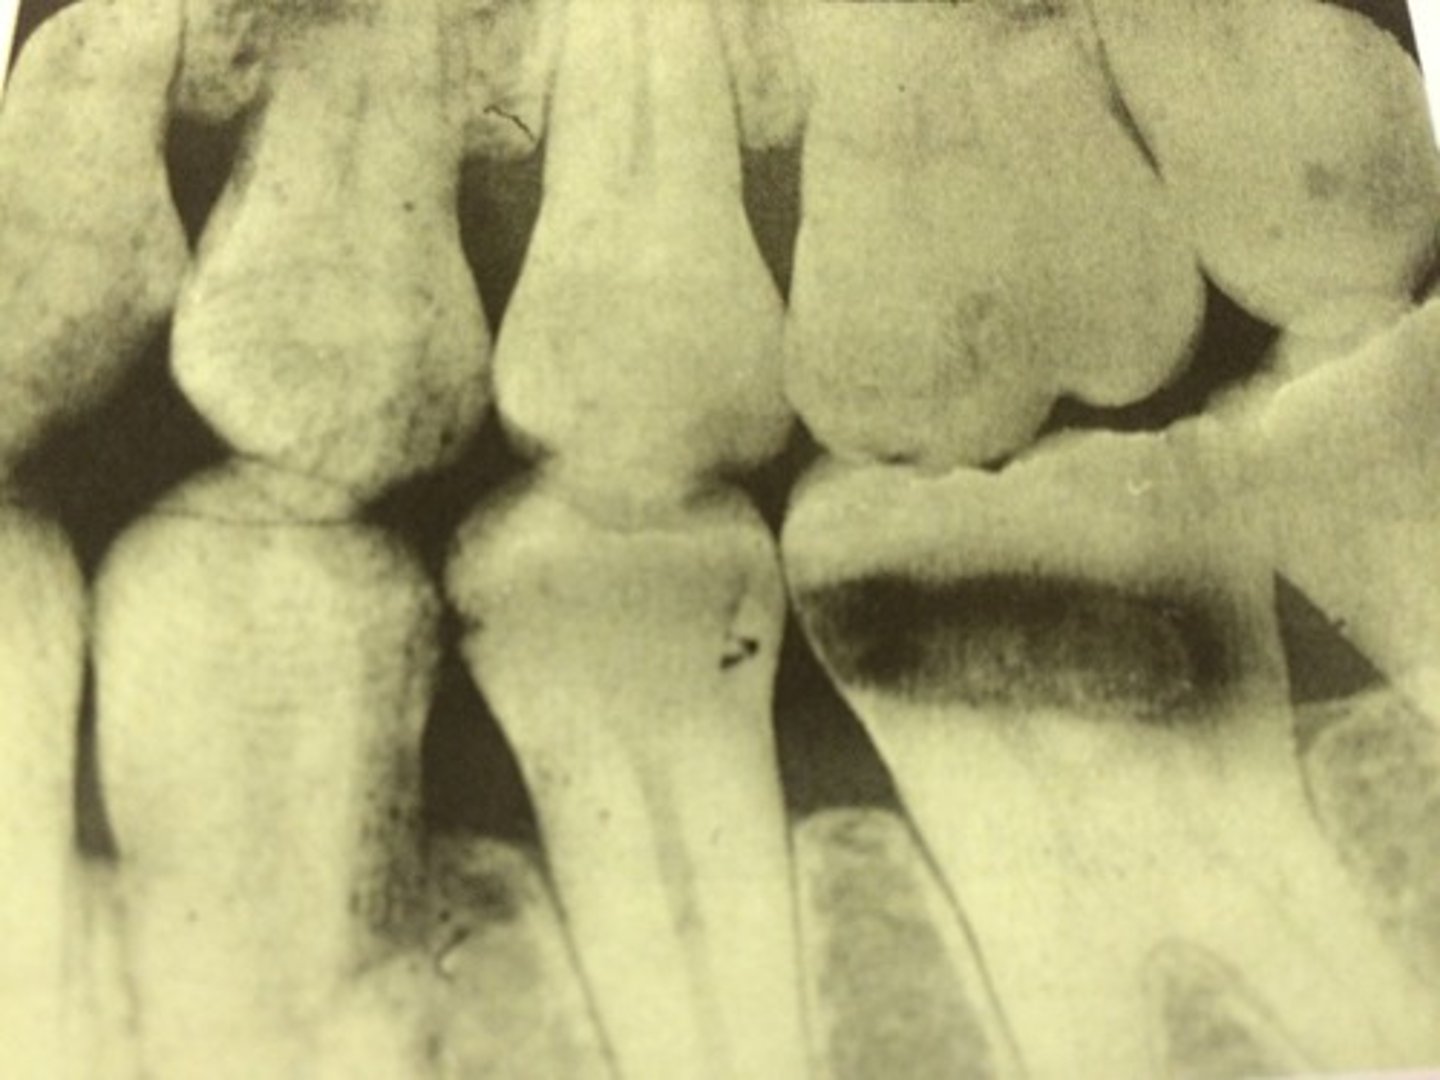

Phalangioma

Distal phalanx of the finger is seen in the radiograph

<p>Distal phalanx of the finger is seen in the radiograph</p>